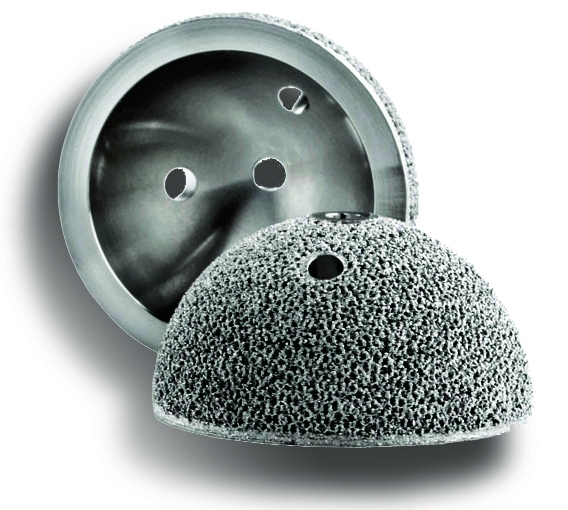

100,000 Patients Later, The 3D-Printed Hip Is A Decade Old And Going

www.odtmag.com

www.odtmag.com

3d hip printed medical implants implant lima printing orthopedic devices technology industry ge corporate bone patient specific strong going titanium

100,000 Patients Later, The 3D-Printed Hip Is A Decade Old And Going

www.odtmag.com

www.odtmag.com

hip 3d printed decade patients strong later going old

100,000 Patients Later, The 3D-Printed Hip Is A Decade Old And Going

www.ge.com

www.ge.com

delta replacements fabbaloo